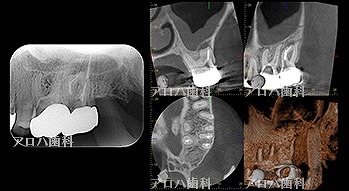

case9

自費の補綴

遠心口蓋側に限局性の深いポケット

上顎洞に波及している。